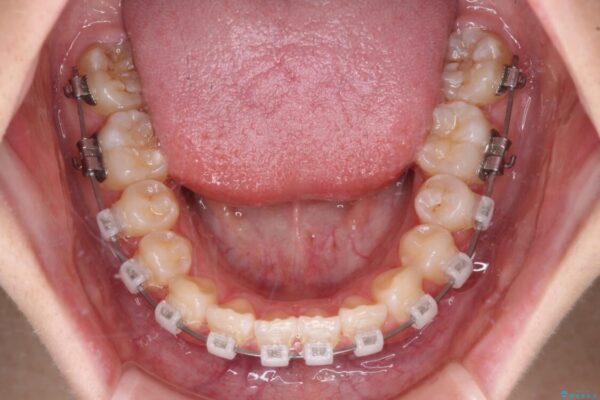

クリアブラケット

治療途中

• インビザラインは使える自信がない ワイヤー装置にて矯正治療 治療途中画像